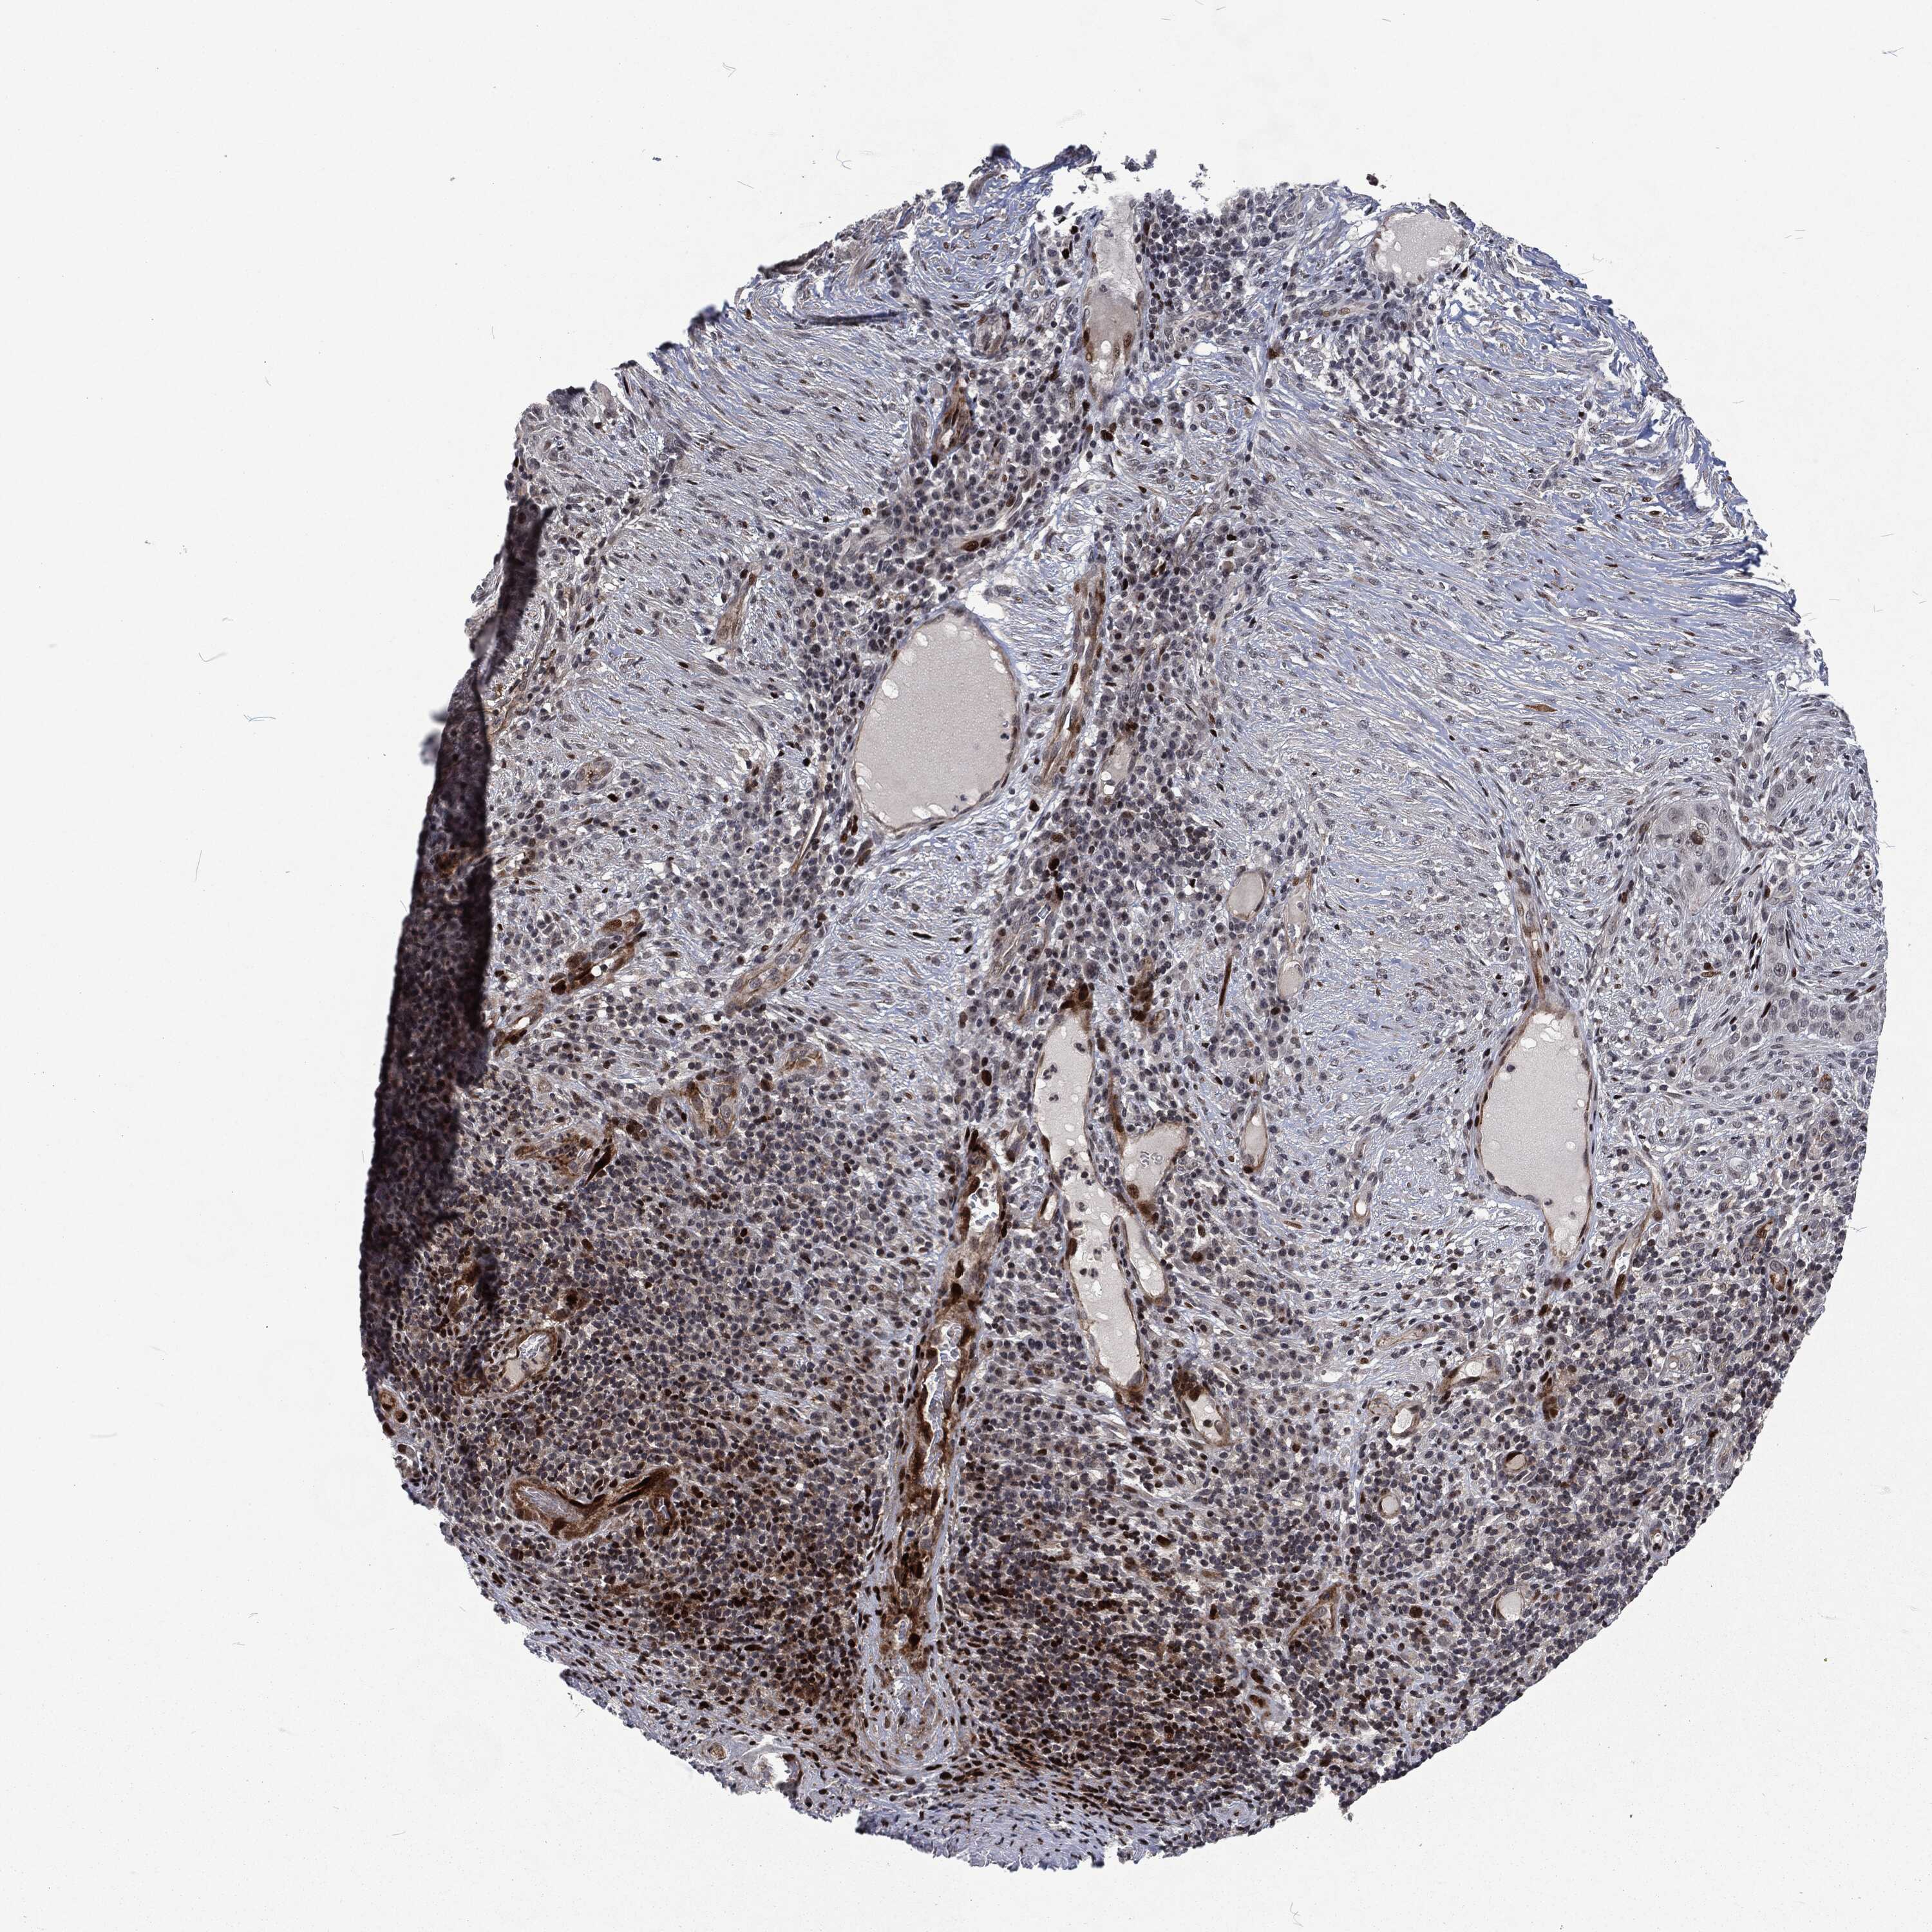

SKIN CANCER - Protein expressioni

A mouse-over function shows sample information and annotation data. Click on an image to view it in a full screen mode. Samples can be filtered based on level of antibody staining by selecting one or several of the following categories: high, medium, low and not detected. The assay and annotation is described here.

Antibody stainingi

Antibody staining in the annotated cell types in the current human tissue is reported as not detected, low, medium, or high, based on conventional immunohistochemistry profiling in selected tissues. This score is based on the combination of the staining intensity and fraction of stained cells.

Each image is clickable and will lead to virtual microscopy that enables deeper exploration of all samples and also displays staining intensity scores, fraction scores and subcellular localization as well as patient and tissue information for each sample.

HPA018530

Staining

High

Medium

Low

Not detected

Basal cell carcinoma